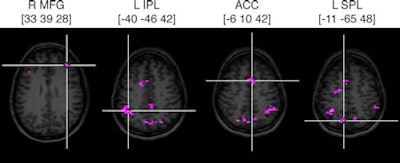

![]() |

| Axial images of seven brain regions with crosshairs indicating center of mass and brain activity when switching or repeating tasks. Images courtesy of the Proceedings of the National Academy of Sciences and the University of New Hampshire. |